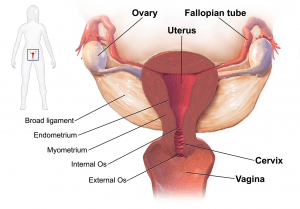

Pelvic anatomy.

- Also known as endovaginal ultrasound

- Used to evaluate female reproductive organs including uterus, ovaries, fallopian tubes, cervix, and vagina